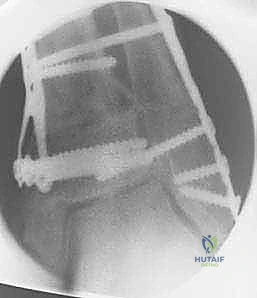

5. التثبيت الصلب وزراعة الطعم العظمي

في حالة "فتح الإسفين"، يتم وضع طعم عظمي (يؤخذ غالباً من عظم الحوض للمريض أو طعم صناعي متقدم) لملء الفراغ. بعد ذلك، يقوم الدكتور هطيف بتثبيت العظم في وضعه الجديد القويم باستخدام شرائح معدنية تشريحية مصممة خصيصاً لهذه المنطقة (Anatomical Locking Plates) ومسامير قوية. هذا التثبيت الصلب يضمن التئام العظم بشكل صحيح.